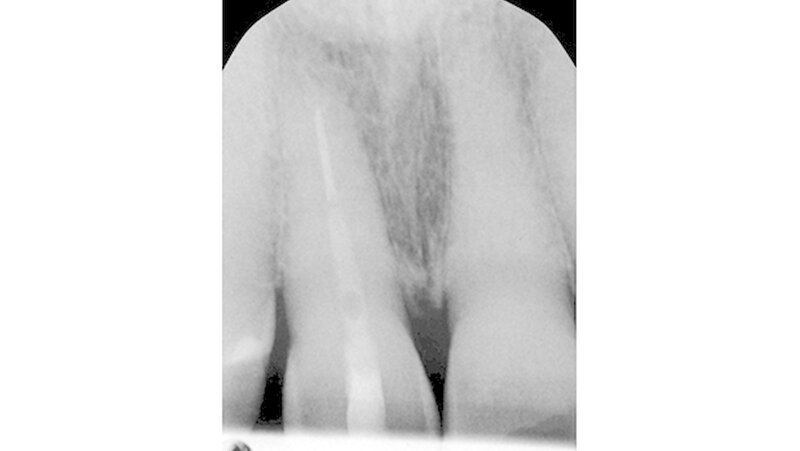

Bei der Vorstellung in der Poliklinik zeigte sich klinisch eine Schmelzfraktur auf der bukkalen Fläche des Zahns 11 (Abbildung 1). Die Messung der Taschensondierungstiefe (TST) ergab an dieser Stelle lokal begrenzt einen Wert von 7 mm (Abbildung 2). An allen übrigen Messpunkten lag eine physiologische TST von 3 mm vor.